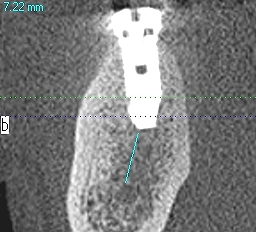

埋入後CTになります

6番あたりになります